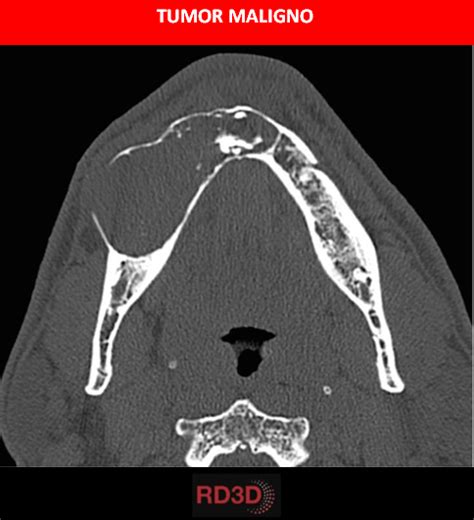

A continuación, se presenta una descripción general de los distintos tumores malignos que afectan a la mandíbula:

- Carcinoma de células escamosas: Es el tipo más frecuente de cáncer de mandíbula y suele extenderse desde los tejidos adyacentes. Un subtipo menos frecuente es el carcinoma escamoso intraóseo primario, que es una neoplasia poco frecuente de los maxilares.

- Osteosarcoma de mandíbula: Es una forma de cáncer óseo poco frecuente, representando menos del uno por ciento de todos los tumores malignos de la cavidad oral.

- Ameloblastoma: Es un crecimiento tisular típicamente benigno que excepcional y raramente evoluciona a tumor maligno. Se origina a partir de ameloblastos e invade agresivamente los espacios de la médula ósea.